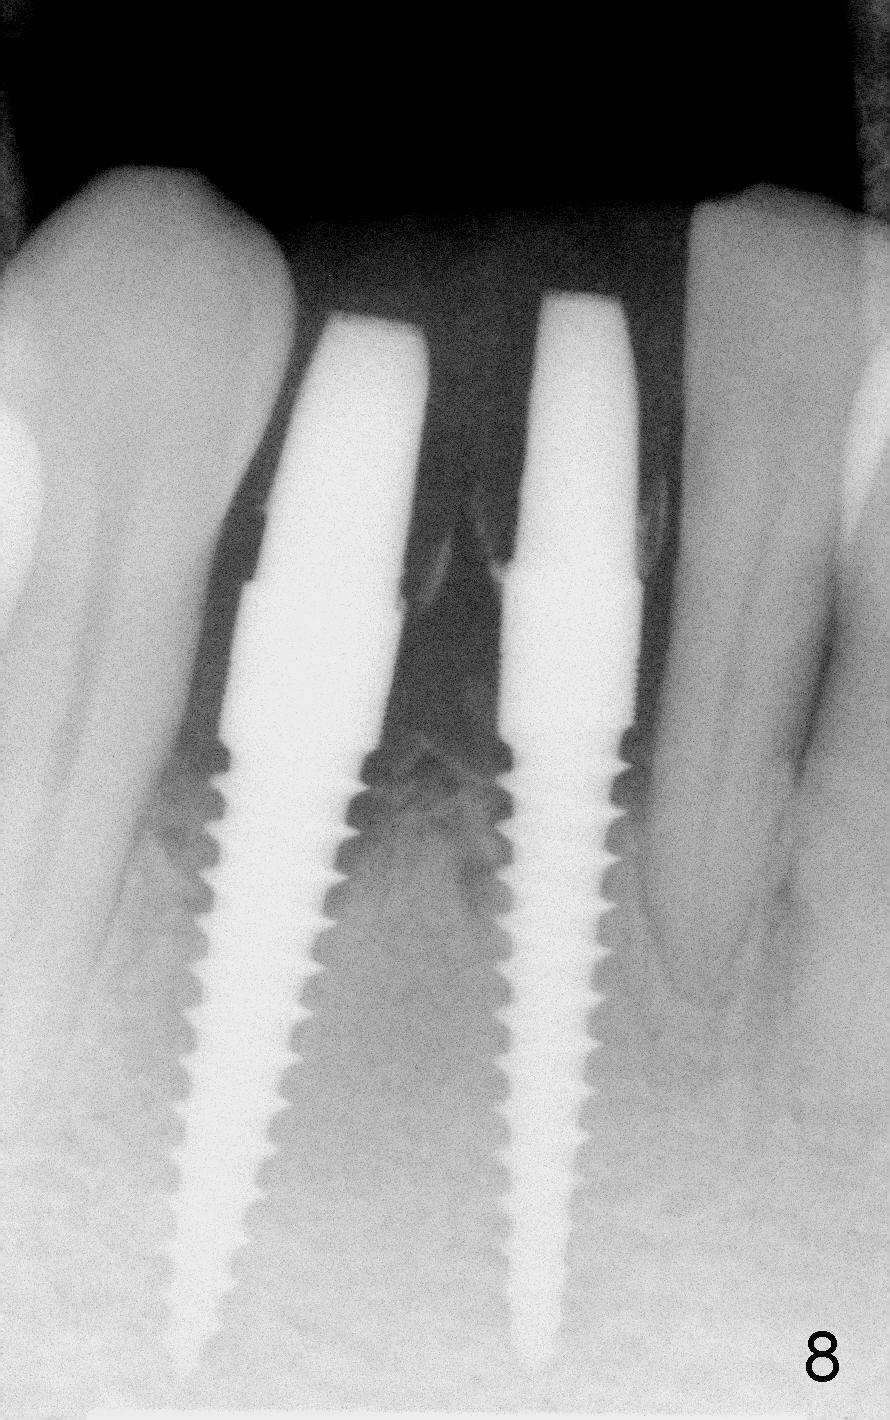

A 60-year-old lady wants to remove 2 mobile lower right incisors (Fig.1,2; with infection at the lateral (>)). Immediate 1-piece implants are placed (Fig.3,4): 3x17 mm at the central, 3.5x17 mm at the lateral. Insertion torque is > 60 Ncm for the implants. No bone graft is placed. After prep (Fig.5), two separate provisionals are fabricated (Fig.6). The one at the lateral incisor looks bulky at the cervix, because of the oversized implant for the site (over-engineering). Use of smaller implant (3.0 (instead of 3.5), 2.5 (instead of 3.0) or 2.0 mm) may solve the problem. Seven days postop, the infection resolves (Fig.7 >) with normal-looking papilla (*).

Fig.8,9,10 are taken 4 months postop, immediately and 2 years 2 months post cementation, respectively. They show that peri-implant gaps are reducing. There is no buccal atrophy atrophy 2 years 2 month post cementation (Fig.11 *).